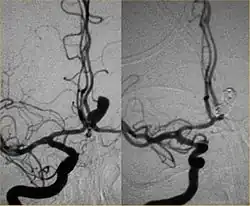

Endovascular repair of cerebral aneurysm

Intra-cranial angioplasty and stent of basilar artery stenosis